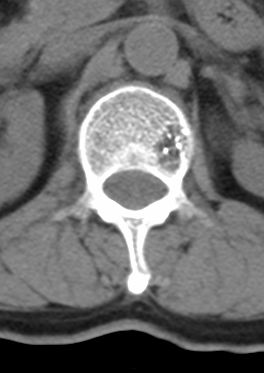

标题: CT22439:腰椎低密度病灶(腰椎血管瘤) [打印本页]

标题: CT22439:腰椎低密度病灶(腰椎血管瘤)

患者 女 54岁 外伤后检查发现l1椎体局部密度减低,请问这是什么病灶?

考虑腰椎血管瘤

椎体内部局限性骨小梁稀疏、粗大改变,周围未见软组织肿块,首先考虑椎体血管瘤。

l1椎体血管瘤可能性大;建议必要时行mri检查。